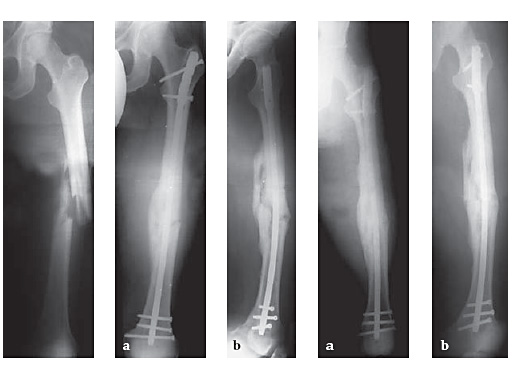

53-year-old malefallen in the busAO Classification 32-B1.1

Case provided by Hermann Bail, Berlin, DE